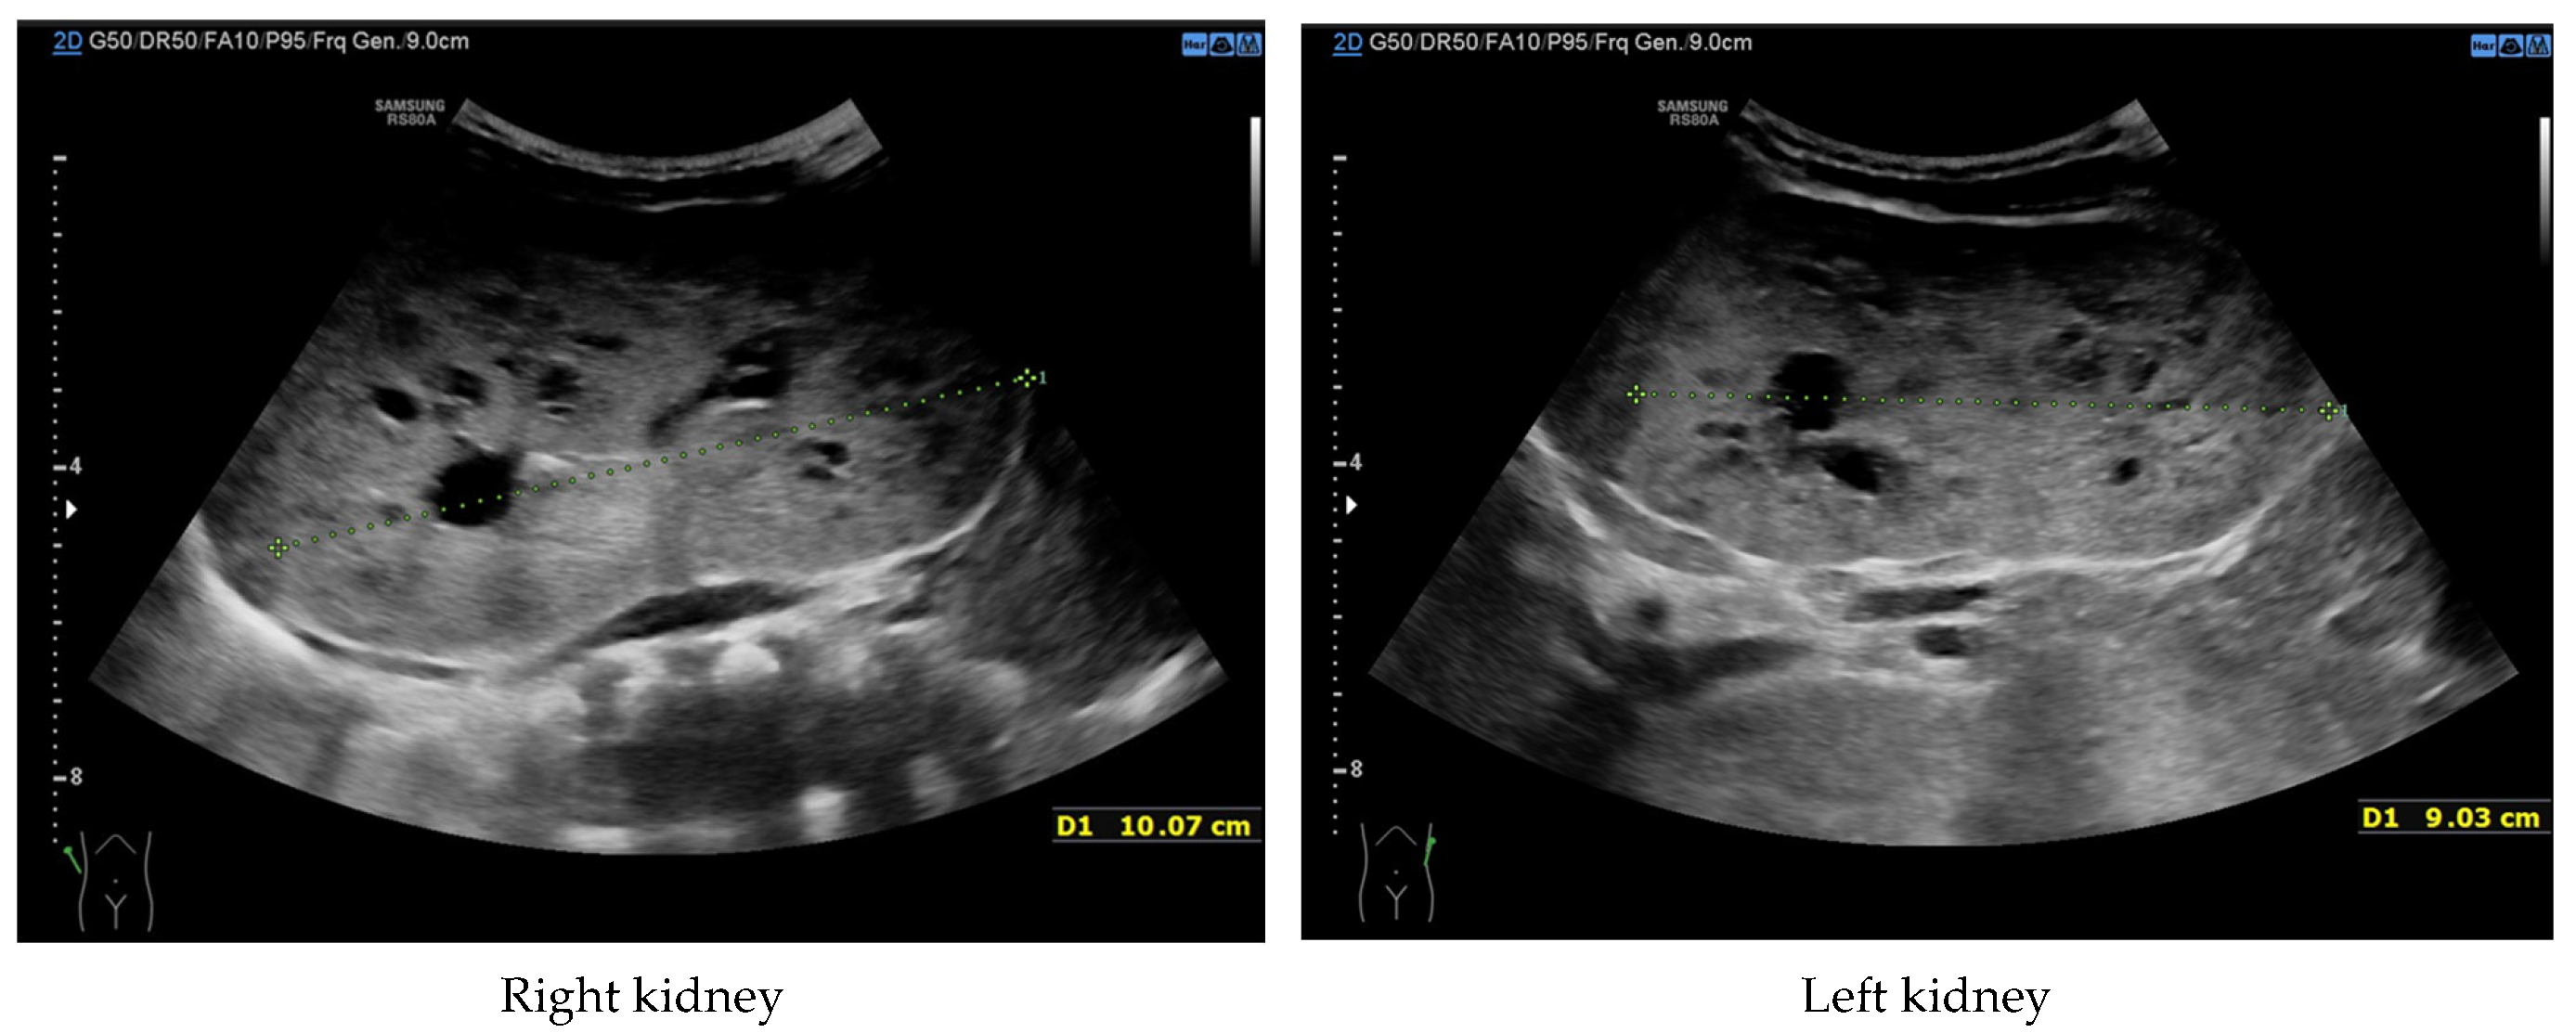

Currently, the boy is 5 years old. The US is similar to the previous one: elevated kidneys length (right: 130 mm (z-score 6.19); left: 133 mm (z-score 6.50)), with increased echogenicity, blurred corticomedullary differentiation, and multiple cysts with a maximum diameter up to 13–15 mm. The liver has a normal size, with numerous cysts up to 16 mm in diameter, with the largest cluster of cysts measuring 43 × 23 × 31 mm (

Figure 3 and

Figure 4). Laboratory tests show increased creatinine 0.79 mg/dL, urea 69,6 mg/dL, cystatin C 1.71 mg/L, uric acid 6.9 mg/dL, urine albumin to creatine ratio (ACR) 118.6 mg/g, and decreased GFR 55 mL/min/1.73 m

2—stage III CKD. Other tests, including electrolytes, liver function, and urinalysis, were normal. The boy demands antihypertensive multi-drug therapy: angiotensin-converting enzyme inhibitors (ACEIs), calcium channel blockers, and beta-blockers.